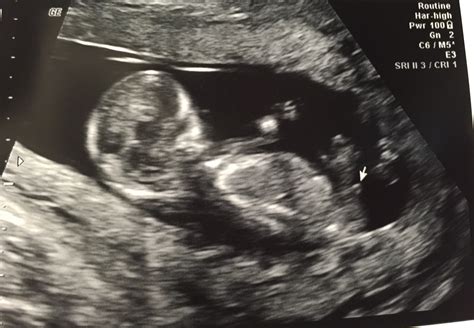

• Visualizing the Baby: At 12 weeks, the baby is about the size of a plum and has distinct features, including a head, body, and limbs. The ultrasound will show the baby’s movements, such as sucking its thumb or curling its toes.

• Anatomy and Development: The ultrasound will show the baby’s major organs and structures, ensuring they are developing normally.